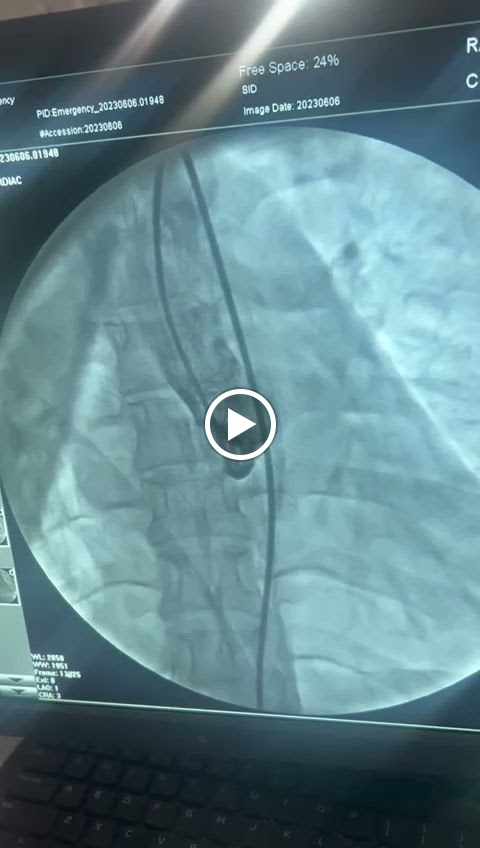

Dr Ashaq Hussain Khandy, MBBS, MD Medicine, DNB Cardiology Senior Interventional Cardiologist in Sahota Super Specialty Hospital in Kashipur, Udham Singh Nagar. Performing heart angiography and angioplasty is a delicate and precise procedure that requires the expertise of a specialized medical professional, typically an interventional cardiologist. Doctor Ashaq is a best choice for conducting heart angiography and angioplasty.